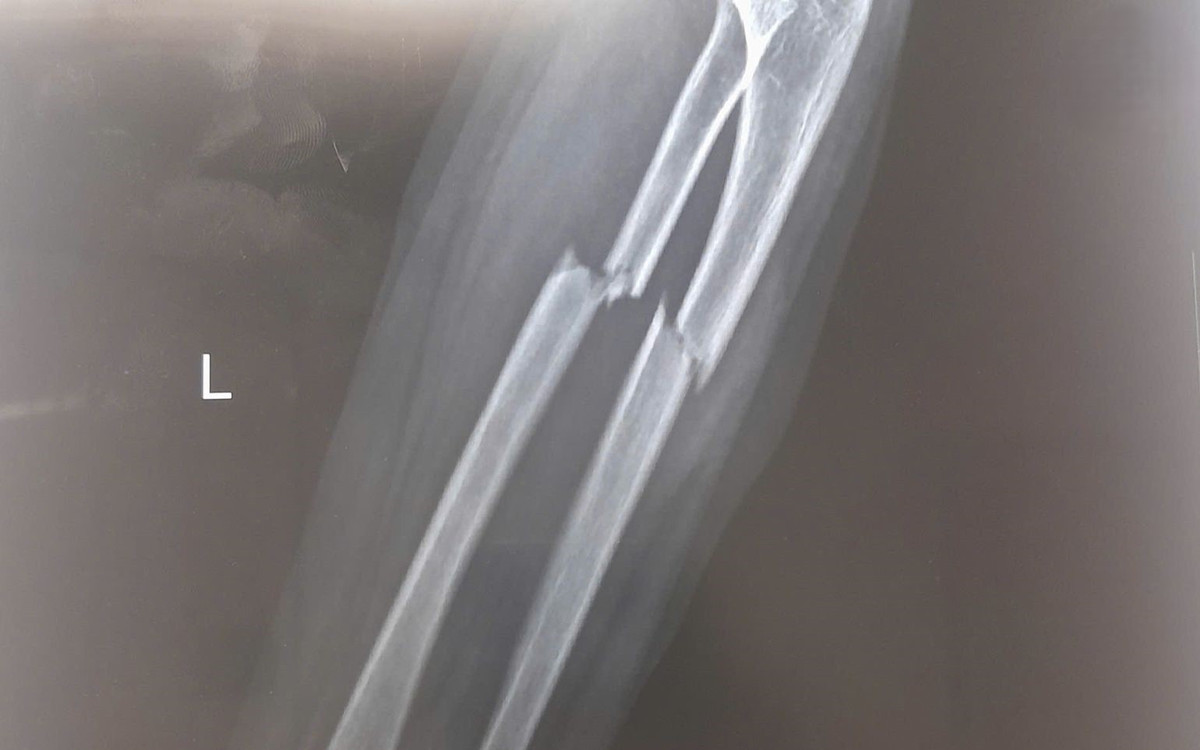

Bệnh nhi N.M.H. (7 tuổi, Bắc Ninh) đến thăm khám tại Bệnh viện Đa khoa Hồng Ngọc trong tình trạng đau nhiều vùng cẳng tay trái, hạn chế vận động sau khi đi xe đạp bị ngã. Kết quả chụp X-quang cho thấy bé bị gãy kín 1/3 trên cả hai xương cẳng tay trái (xương quay và xương trụ), có mảnh xương di lệch.

Theo ThS.BS Trương Xuân Quang, chuyên gia phẫu thuật chấn thương chỉnh hình, Bệnh viện Đa khoa Hồng Ngọc, gãy cẳng tay là chấn thương phổ biến ở trẻ em do đặc điểm yếu dễ gãy khi bị va đập hoặc té ngã. Bệnh nhi H. mới 7 tuổi nhưng nặng tới 40kg tương đương trẻ 15 tuổi. Thể trọng lớn khiến đoạn xương gãy chịu áp lực cao, hình thành đường gãy phức tạp và có di lệch. Thông thường, bó bột là chỉ định ưu tiên trong điều trị gãy xương ở trẻ nhỏ.

Tuy nhiên, vị trí gãy của bé nằm ở 1/3 trên hai xương cẳng tay, khó nắn chỉnh để đưa xương về đúng vị trí giải phẫu, nguy cơ xương liền lệch là rất cao. Bên cạnh đó, việc phải bất động tay suốt 4 - 6 tuần có thể gây hạn chế vận động, dẫn tới cứng khớp và khiến quá trình phục hồi chức năng sau này kéo dài, khó khăn hơn.